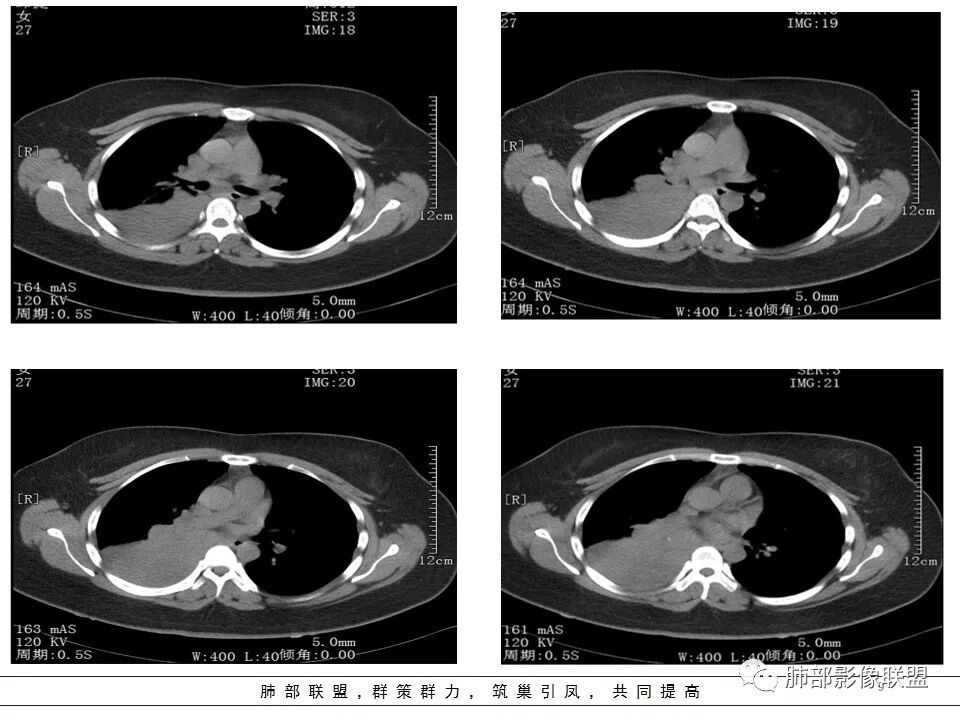

女,27岁,右肺下叶支气管闭塞,圆形软组织肿块和不张肺,增强不均匀强化,见片状坏死,多个纵隔淋巴结肿大,无钙化空洞及卫星灶;考虑恶性占位,肺肉瘤或鳞癌合并肺不张,鉴别诊断:结核,肺脓肿

CT扫描示右肺下叶支气管堵塞,类圆形大肿块伴胸膜下大片肺实变影,增强扫描类圆形肿块延迟强化,见少量坏死,余实变区增强可见内部血管走行。纵隔见肿大淋巴结。考虑为恶性病变伴右肺下叶肺不张

水晶石头 :

患者青年女性,发热6 天,咳嗽、咳痰3天。为黄脓痰。胸部CT:右肺体积稍小,右中间支气管肿物堵塞,中叶、下叶大片实变不张,与正常肺组织分界清楚。增强实变影明显强化,右下肺支气管近心端见类圆形强化结节影,血管纤细,部分支气管显影变细,纵隔淋巴结肿大。结合无呼吸困难症状,病程长。综合考虑低度恶性病变并阻塞性肺炎,类癌可能大,鉴别结核、淋巴瘤。

纵隔淋巴结肿大,以2/4R区、3区为主

这里不知道是不是内乳的淋巴结?

如果是内乳淋巴结,代表淋巴瘤

本病例特点是中叶病灶和下叶病灶不一样,支气管腔内的病灶又是怎么样的呢?我们要是有沿支气管重建的冠状位、矢状位会更有利于分析。第一,中叶病灶明显粘液样改变、低密度,且低密度区有占位效应、膨隆,确实要考虑粘液表皮样癌。第二,中叶和下叶支气管显示不出来,但血管显示出来了。中叶病灶血管稀疏、细小,下叶病灶血管粗大、走形正常。朝外肺不张实变,不是单纯的肺不张,肺不张一般体积明显缩小、血管聚拢,该病例肿瘤于其中成分不一样,所以上叶部分病灶考虑为下叶病灶占位效应及膈面向上推压引起,中叶萎缩。综合腔内堵塞、纵隔淋巴结肿大要考虑恶性。

支气管层面位置朝下强化明显,支气管腔内、远端是有差异的,腔内哪些是粘液?哪些是肺组织?是单纯实变?还是合并感染?还是外围都是病变?支气管腔内病变?

该病灶明显实变,需鉴别是内朝外,还是外朝内病变。该病灶内血管走形自然,肺门区血管无明显受压移位,且非起源于胸膜,不张肺组织或者不张肺组织夹杂炎性病变。而非典型肺炎型肺癌及外朝内的其他恶性病变。

内朝外病变是支气管腔内病变?还是支气管周围病变呢?如果支气管周围大恶性肿块灶,那其内血管也不应走形自然,应杂乱无章,所以只能是腔内病变引发支气管周围病变。